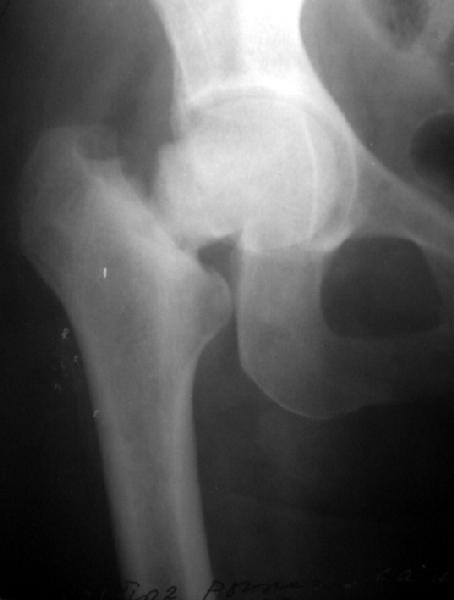

Женщина лет 40 переведена к нам из городской больницы с переломом шейки бедра.

Упала дома 5.11.02. С ее слов, в послдений год лечилась консервативно от якобы коксартроза с этой же стороны. Снимков не делали. Этот сустав болит последние несколько месяцев. На снимках обращает на себя "замыленность" краев. Не усталостный ли это перелом? Дама полноватая. Ограничения амплитуды движений до травмы она не отмечала.Мнения о тактике у нас разошлись в диапазоне от остеосинтеза винтами до эндопротезирования, с остеотомиями между ними. Помогите, пожалуйста, обосновать выбор.

Мне кажется с этой женщиной надо прежде всего хорошо поговорить. Перелом выглядит несвежим (не менее 4-6 месяцев) и не патологическим. Усталостный ведь тоже патологический! По-моему, был у неё импактный относительно устойчивый перелом шейки, образовавший фиброзный N-Union. Поэтому были у неё боли и "коксартроз". При последнем падении она его дез-импактировала.

To me the whole head, neck and adjacent acetabular area look sclerotic.

This one was made at the initial hospital two days before transfer.

Прилагаю еще одну рентгенограмму - обзорный снимок таза от 11 ноября, еще до перевода к нам. Ранее были посланы снимки, сделанные 13 ноября

уже у нас.